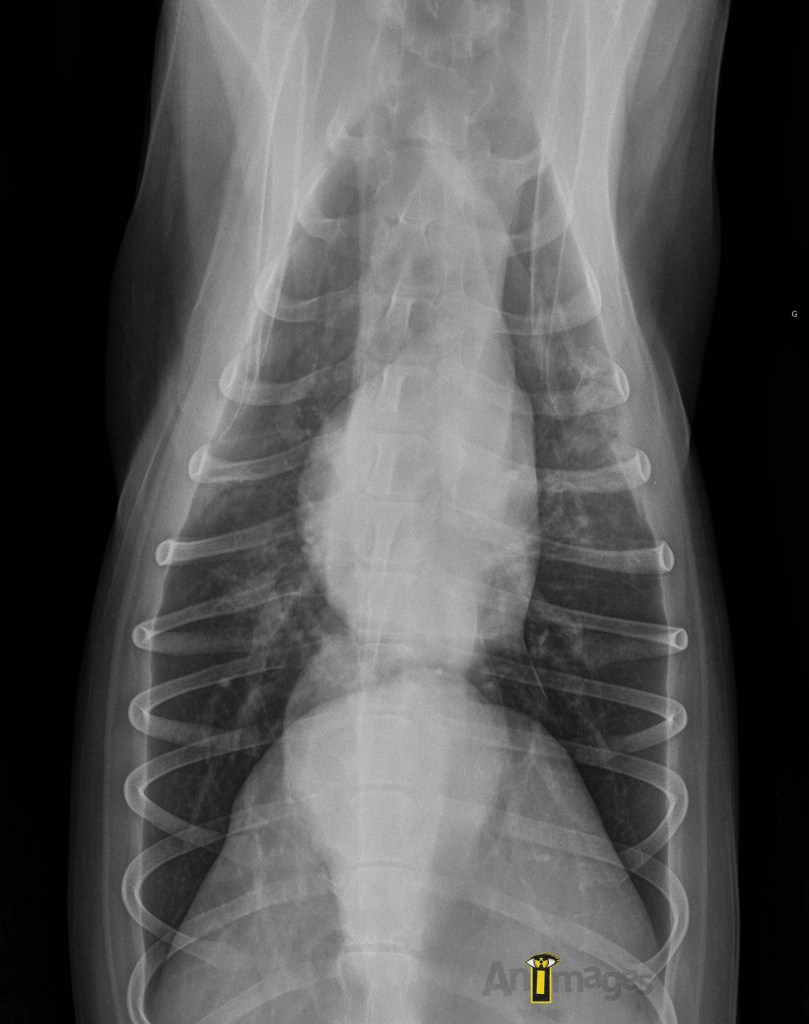

Ventrodorsale